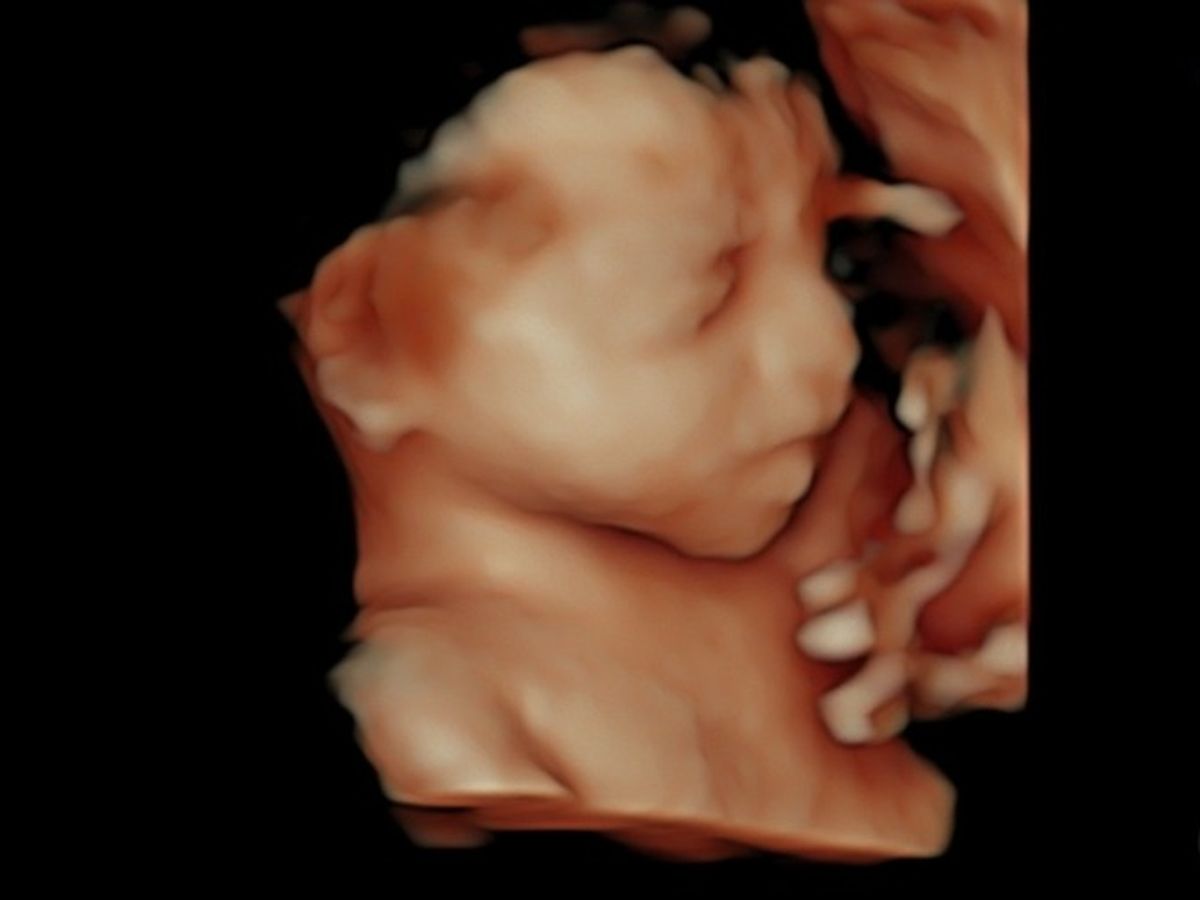

Our family is setting up this donation account on behalf of Jasen and Amanda Leonard and their baby girl, Alayna, who is expected to arrive in November. In the womb, Alayna was diagnosed with a condition known as CDH “Congenital Diaphragmatic Hernia”, which basically causes her organs to take space in her lungs, which prevents lung development. Baby girl's case of CDH has been classified as serious. She will need surgery shortly after birth and is expected to be in the ICU for at least 3 months.